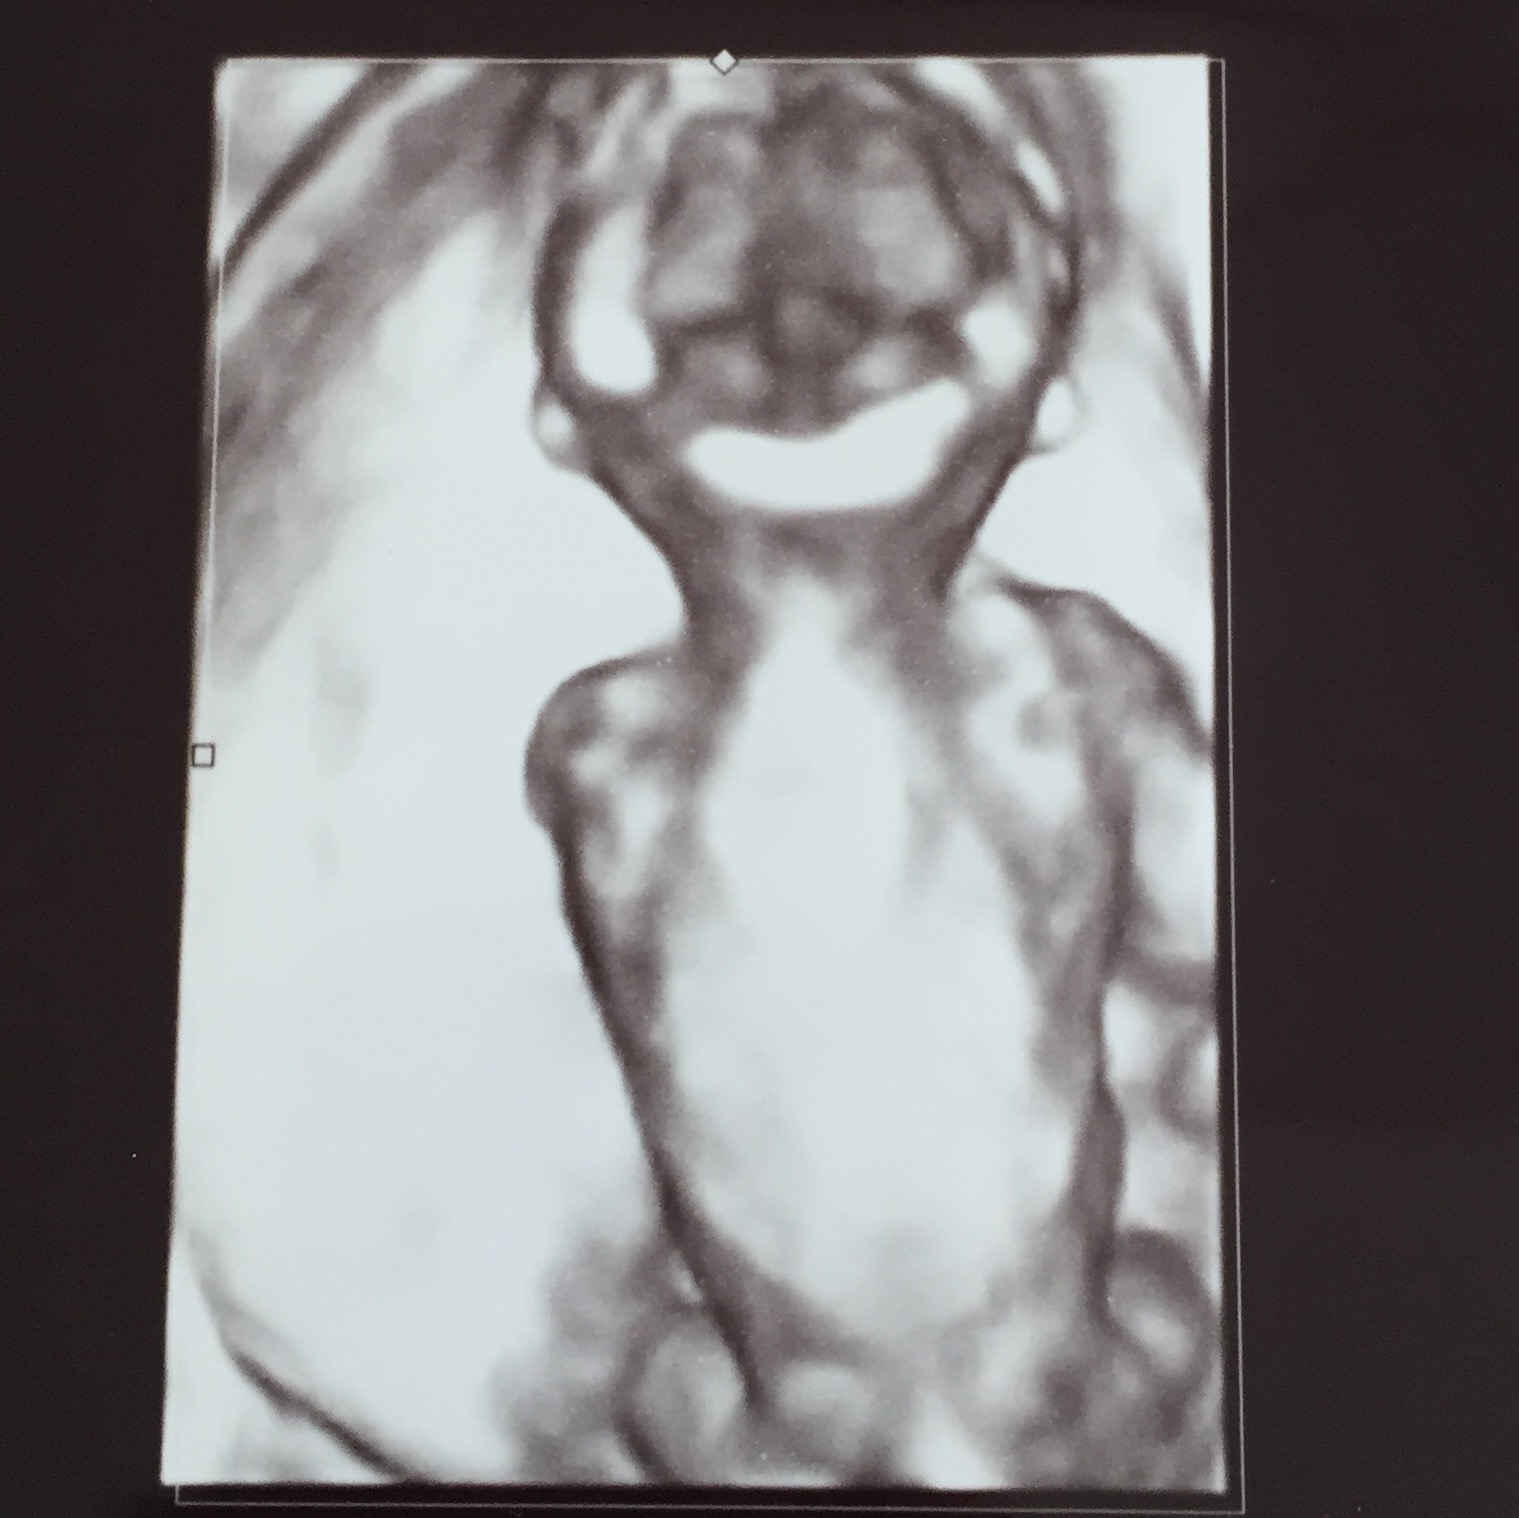

4Dも撮ってもらえましたが、なんと4Dに切り替えるタイミングで背中を向ける我が子( ;∀;)

ええええお顔見せてよおおおおお( ;∀;)

旦那は「えっこの一瞬の間に何が…」と残念そう。

エコー写真